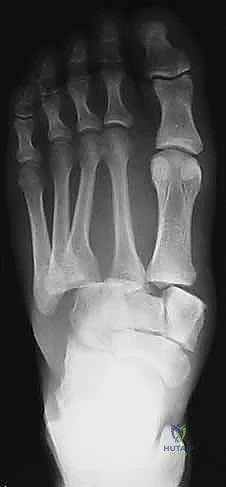

2. التصوير بالأشعة السينية (X-Rays) مع تحميل الوزن

الأشعة السينية العادية قد لا تظهر الإصابة إذا لم تكن العظام مزاحة بشكل كبير. السر يكمن في طلب أشعة سينية أثناء وقوف المريض وتحميل وزنه على القدم المصابة (Weight-bearing X-rays).

* يبحث الدكتور هطيف عن "علامة الفليك" (Fleck Sign)، وهي قطعة عظمية صغيرة مكسورة ومسحوبة من قاعدة المشط الثاني أو العظم المسماري الإنسي، وهي دليل قاطع على تمزق رباط ليزفرانك.

* كما يتم قياس المسافة بين قاعدة المشط الأول والمشط الثاني. أي اتساع يزيد عن 2 ملم يُعتبر غير طبيعي ويشير إلى عدم الاستقرار.